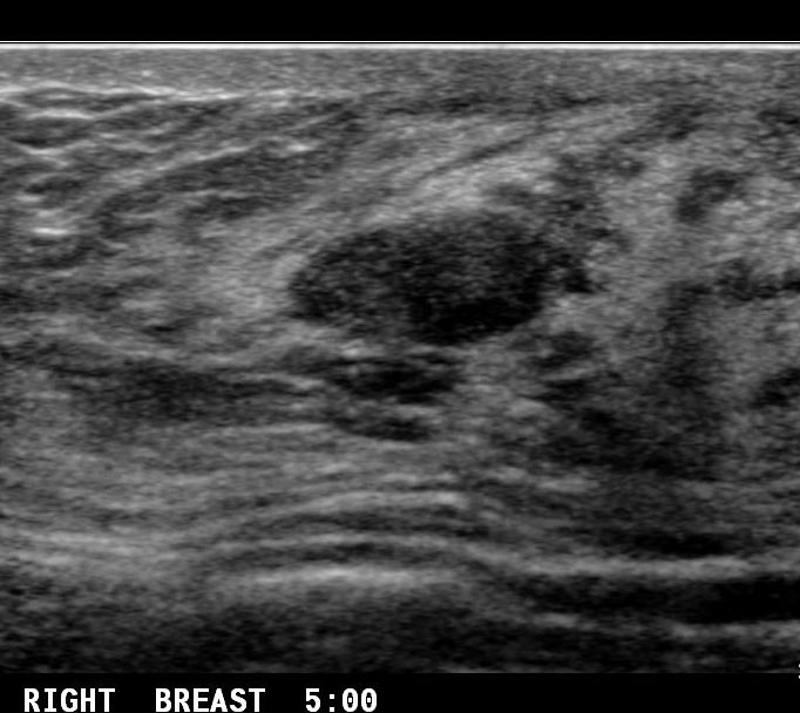

What is a Complex Cysts?

benign breast condition

contain some low level internal echotexture or intra-cystic debris.

Risk of malignancy among complicated breast cysts is thought to be 0.3-2%

What is the Sonographic Appearance of Complex Cysts?

Low to medium echogenicity

Irregular walls

hetertogenous

fluid filled levels

septations

wall thickening

debris

varying degrees of shadowing

What are the presentations of Complex Cysts?